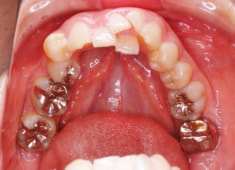

右下7番欠如歯(保存不可能歯につき抜歯)右下8番利用

治療開始時